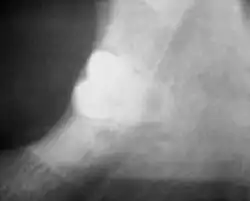

A plain film radiograph allows the proximity of the tooth to the inferior alveolar canal to be assessed. The plain film can be assessed to identify the tooth as high risk If there is; loss of the lamina dura, darkening of the canal and grooving of the root. If the mandibular third molar is deemed to be high risk, a cone beam CT (CBCT) is taken in addition to the plain film. The justification of additional radiography can be justified by the surgeon as it allows them to gain further information regarding the tooth roots and the inferior alveolar canal should the roots be mobilised when transecting.